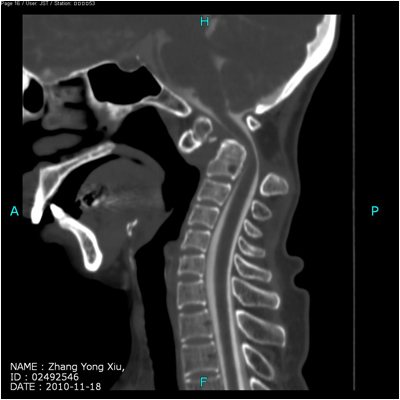

病例一:女性,52岁,诊断:齿突发育不全,寰枢椎半脱位

术前CT图像